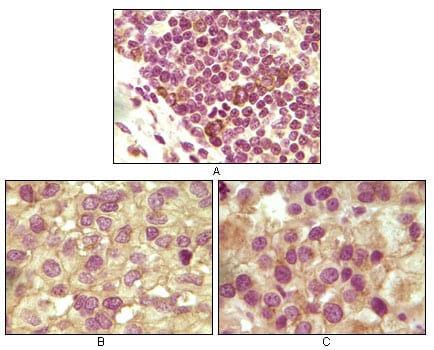

分类: 科研抗体货号: 20106别名: INHA; inhibin, alpha应用: IHC,IF反应种属: Human